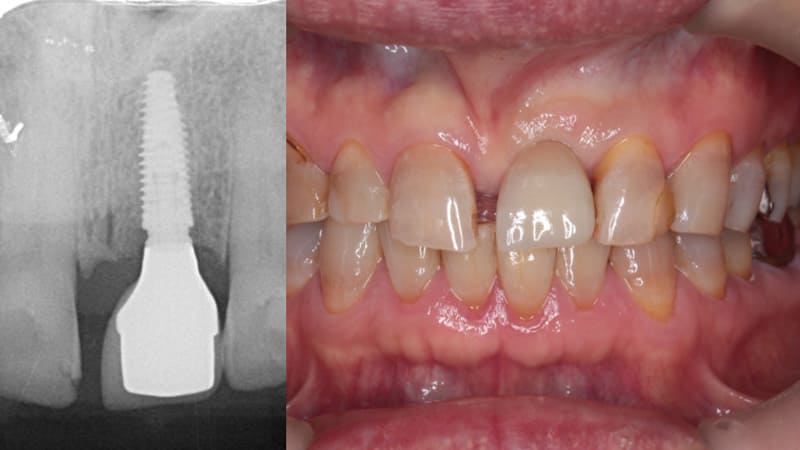

症例②:右下の歯がたまに腫れる

| 治療科目 | インプラント |

|---|---|

| 主訴 | 右下の歯がたまに腫れる |

| 治療期間 | 7ヶ月 |

| 治療費 | 495,000円(インプラント費用¥440,000+インプラントガイド¥55,000) |

| 治療内容 | 抜歯後3ヶ月待ち、インプラントガイドを使いフィクスチャー埋入。その後上部構造を装着した。 |

| 治療のリスク | インプラントが骨と結合しない場合撤去し、再度埋入が必要。噛み合わせに問題ある場合骨吸収を起こすためナイトガード装着をお願いすることがある。また定期的なメンテナンスで歯肉の炎症と咬合のチェックが必要。 |